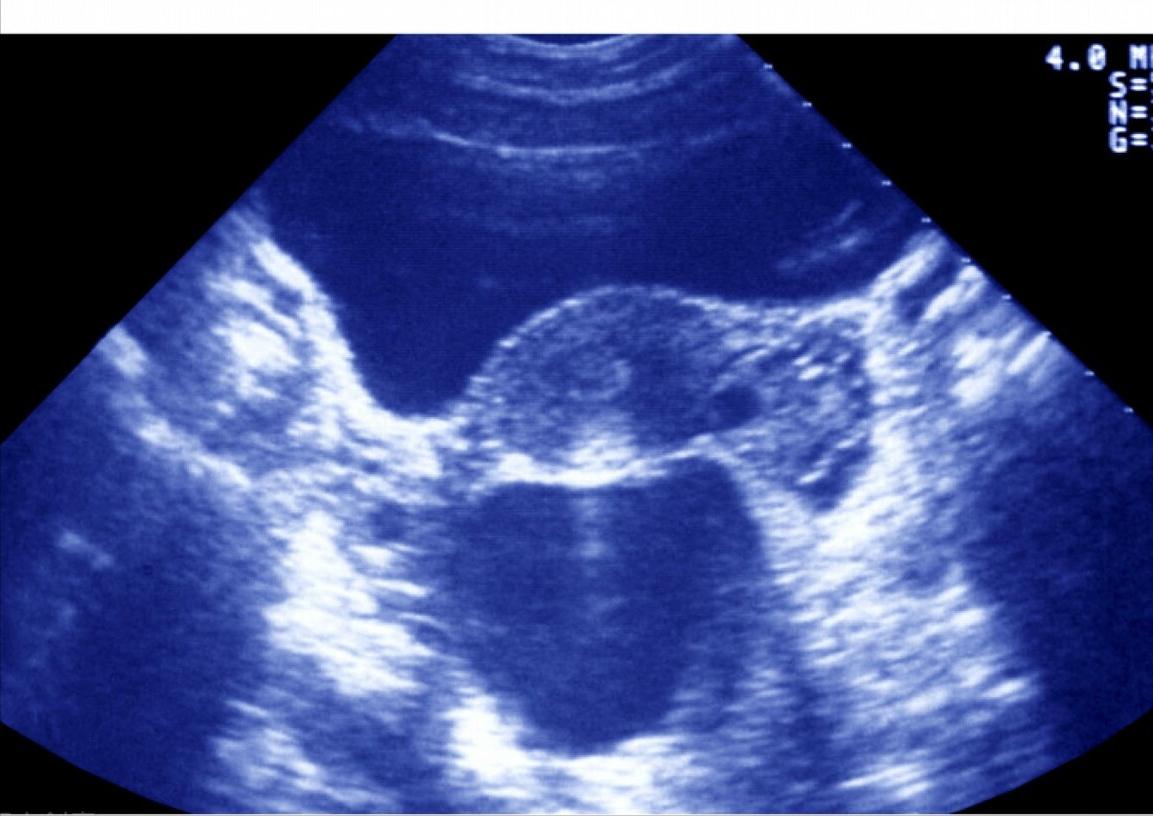

(一 )返流型:这种类型的输卵管积水通常量比较多,阴道超声表现为积水量多,患者在排卵期经常会有阴道水样分泌物流出,就要警惕输卵管积水经常返流入宫腔并从阴道流出。这种返流是严重影响胚胎着床的。即使胚胎移植前1-2天抽出来,但经常还是有少量残留,即使一点点的残留积水也会返流入宫腔,对胚胎着床产生不利的影响。表现为反复着床失败。

(二) 不返流型:有的患者存在输卵管积水,但是积水量通常不大,而且处于静态不增加的状态,积水也不会返流进入宫腔。这类患者在取卵的时候同时抽吸输卵管积水,然后进行新鲜胚胎移植,还是有一定的临床妊娠率。